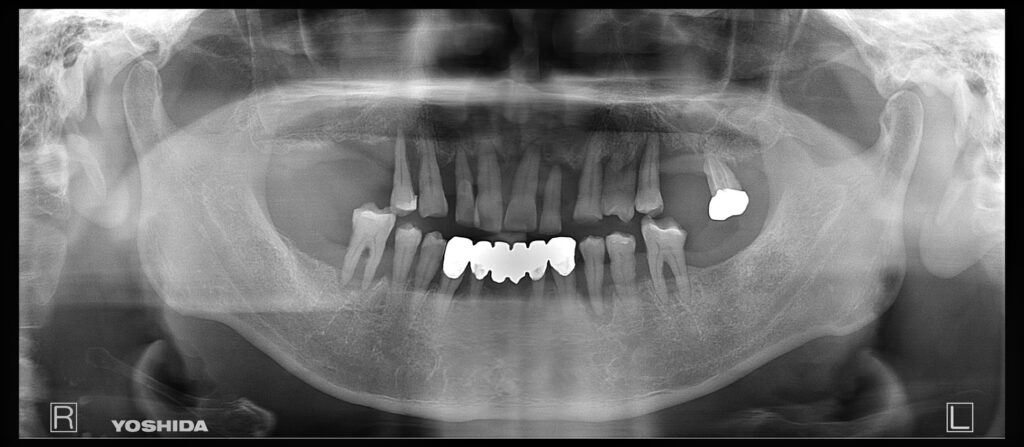

実際の症例です。

レントゲン写真上でも全顎的に重度の歯周病と診断して、IOD治療を選択されました。

残存歯を抜歯後、上顎は4本、下顎は2本インプラントを埋入しました。